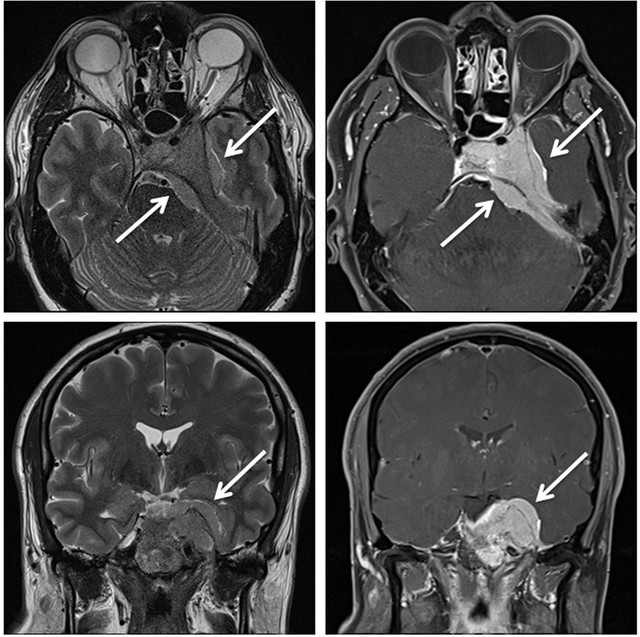

Mrt : Kuala Lumpur’s New MRT Map Alignment. ~ .: Property … / Support more model(qualcomm and … Retinoblastom (MRT/T2) – DocCheck

Retinoblastom (MRT/T2) – DocCheck MRT: Posterior-Hirninfarkt – DocCheck